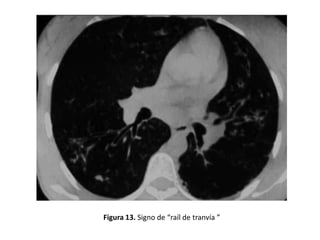

• Pueden visualizarse asimismo bronquios dilatados

dando lugar al signo del "raíl de tranvía". (Figura 13)

Figura 13. Signo de “raíl de tranvía ”

Clasificación morfológica de las

bronquiectasias

• Cilíndricas:

– Son las más frecuentes.

– Los bronquios están mínimamente dilatados de

manera uniforme, no adelgazan su diámetro al

progresar las generaciones y pueden verse sus

paredes como líneas paralelas en cortes

longitudinales (Figuras 10, 13 y 23).